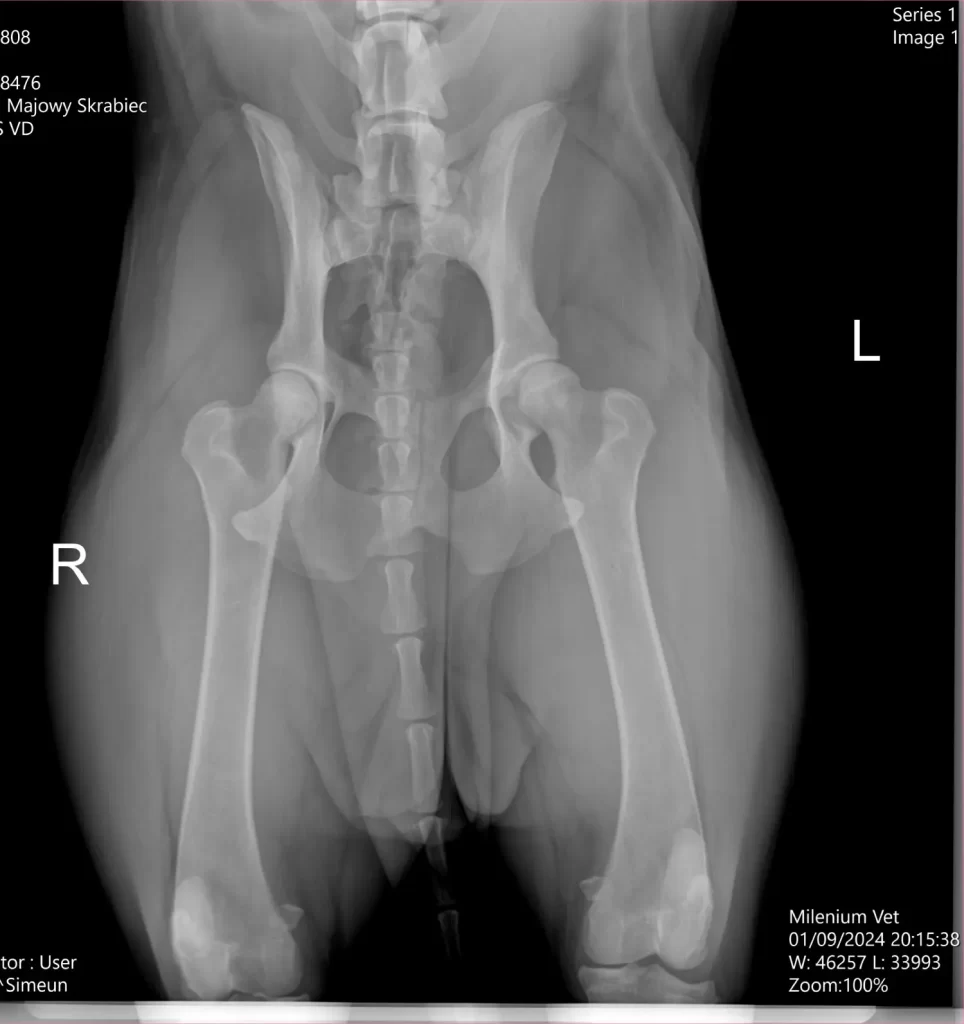

Upitan na koji način se displazija pasa dijagnostikuje, dr Panić naglašava da se dijagnostika displazije kukova i laktova obavlja kliničkim pregledom, ali pošto se ona smatra i skrivenom manom, a da bi se donela konačnu dijagnostiku displazije svakako je neophodno uraditi ortopedski pregled i RTG dijagnostika kao jedan od najpouzdanijih metoda u donošenju konačne dijagnoze. Znači za konačnu dijagnostiku bazira se na kliničkoj slici psa, ortopedskom pregledu i radiološkoj dijagnostici. Kada je reč o rasama pasa, dr Panić naglašava da se displazija može javiti kod svih rasa pasa, ali najčešće se manifestuje kod velikih i krupnih rasa poput nemačke doge, labradora, nemačkih ovčara, bernadnica, rotvajlera. Faktori koji dovode do displazije pored genetiku su i prekomerni rast, prekomerna težina, neizbalansirana ishrana, kao i prekomerno vežbanje, a koji mogu povećati genetsku predispoziciju.

Zato dr Panić naglašava da je veoma bitno da se vlasnik, ukoliko primeti neke od gore navedenih simptoma što pre javi svom veterinaru. Veterinar će na osnovu dijagnostike rtg snimka, proceniti o kom stepenu displazije se radi, da li je to neki blaži oblik ili teži stepen displazije. Shodno nalazu i dijagnostici veterinar će dati preporuku o daljem toku lečenja. Kod blažih oblika se često sprovodi konzervativno lečenje (medikamentima), dok je kod ozbiljnijih displazija potrebno nekada pristupiti I hirurškom zahvatu.